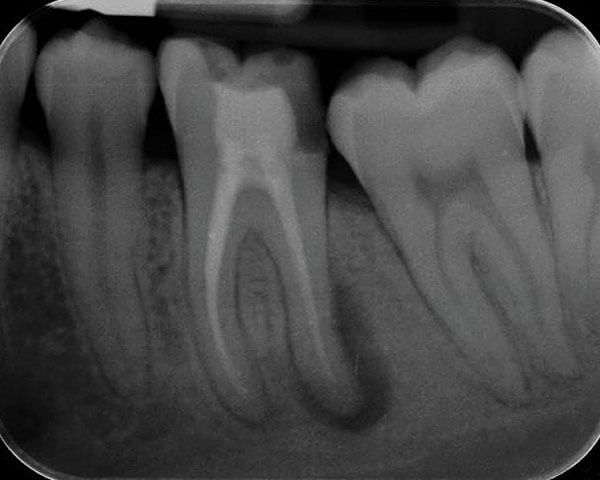

2. 歯の内部が感染して炎症を起こし、根っこの先端が膿んできた場合(根尖病巣といいます)

この病気の場合は歯の根っこの近くあたりがプクッと腫れます。この腫れは膿のかたまりで、 膿が自然に出てる場合は膿んでても痛みを感じない場合もあります。反対に膿が骨の中にこもってしまった場合は、かなりの激痛を感じます。

治療法は、基本的には膿を出します。原因が歯の根っこの内部にあるため、歯の内部を徹底的に洗浄してばい菌を追い出し、その後、新しくばい菌が入らないように根っこの内部に薬をつめます。

治療前。歯の根に膿がたまっています。